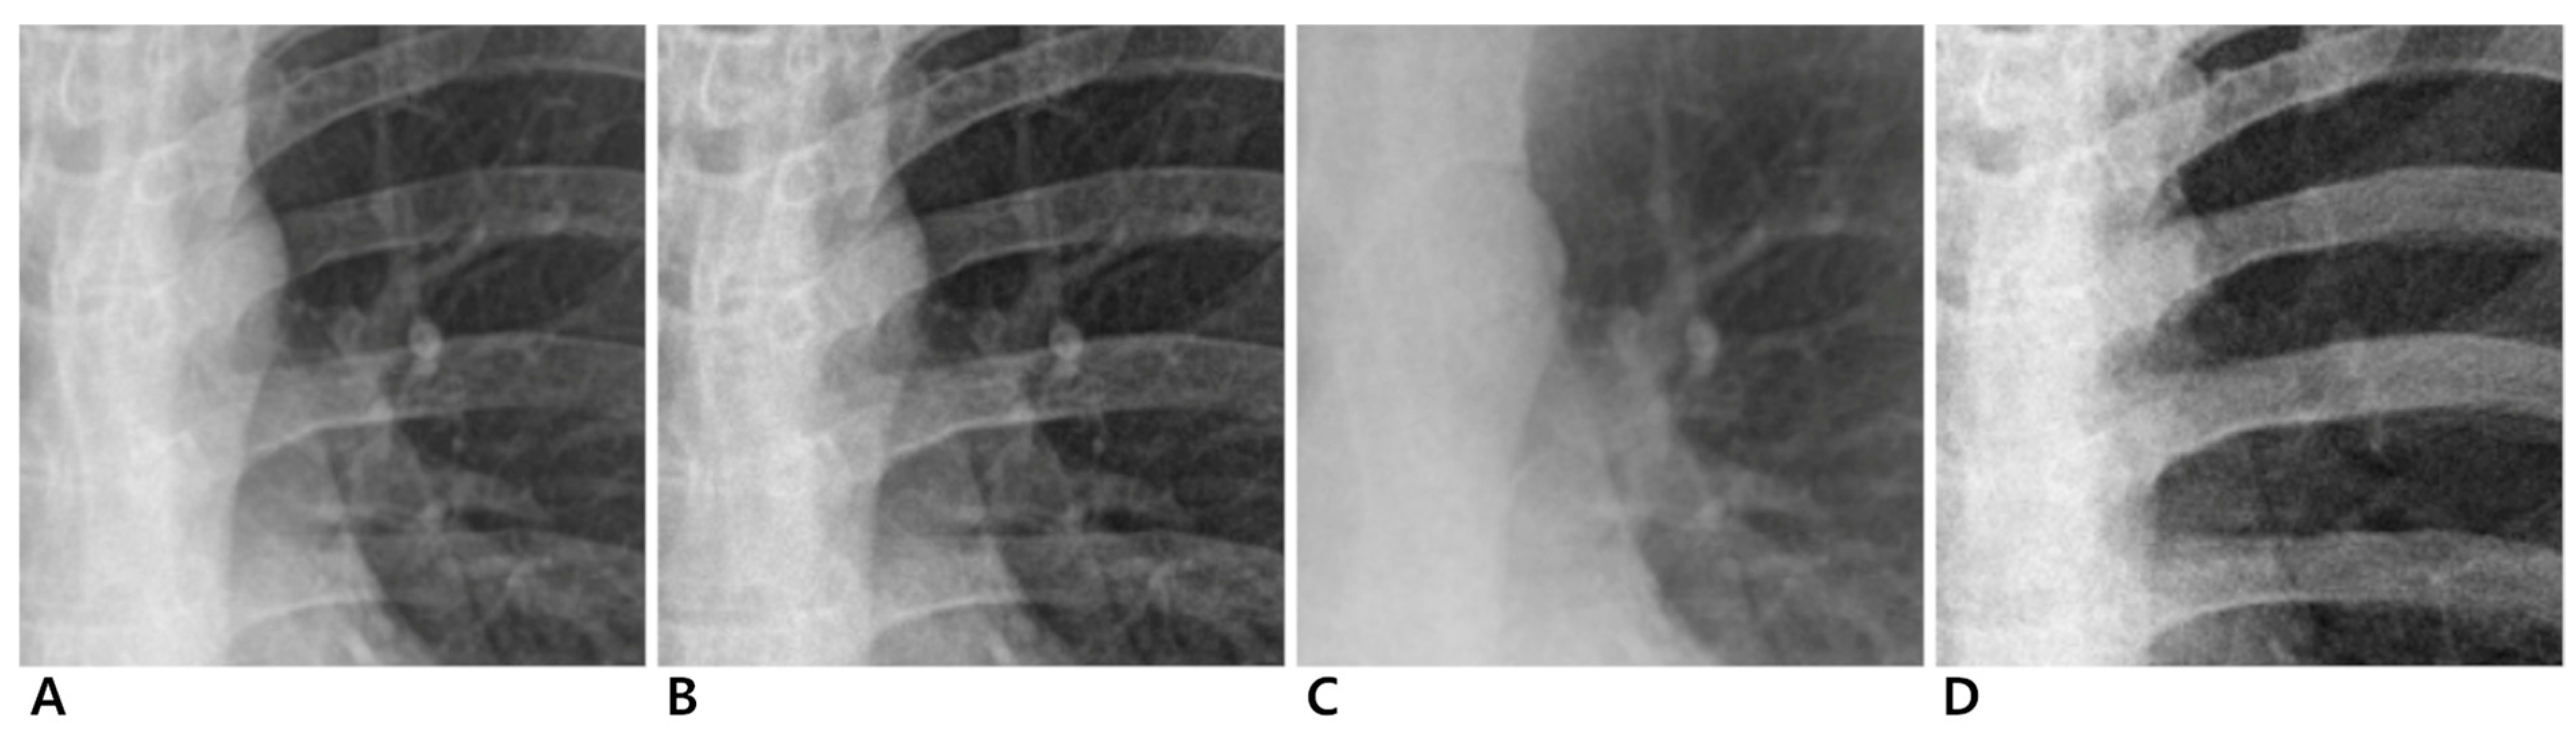

3.2.1. Conventional Standard vs. Enhanced Standard Images

3.2.2. Conventional Standard vs. Soft-Tissue-Selective Images

3.2.3. Conventional Standard vs. Bone-Selective Images